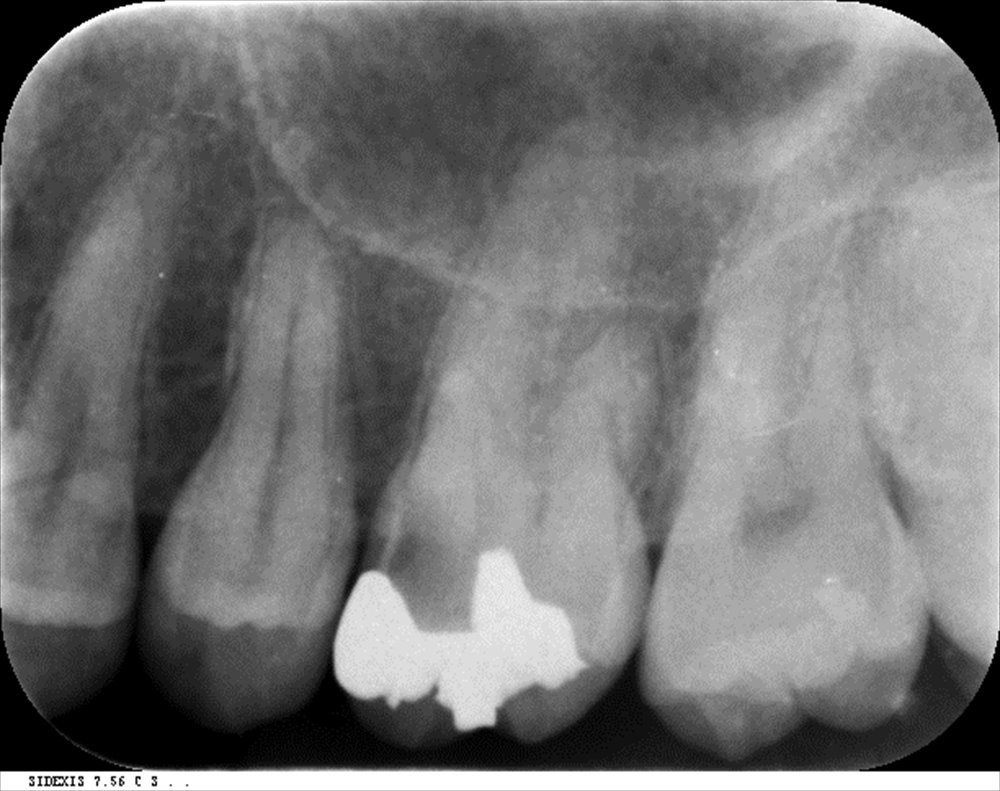

この方は詰め物の中(内部)で虫歯が発症。

左上6番に大きな虫歯。

話は戻りますがこの方はキャンセル待ちで重症の虫歯の処置が出来ました。内部は

神経が腐っていて痛そうでした。